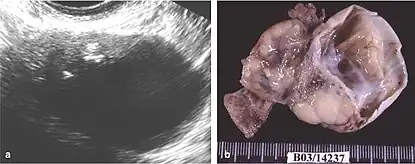

The difficulty in screening for SCC revolves around the creation of effective strategies with a positive predictive value. The timing aspect is crucial due to the lack of a specific timeframe for the onset of invasive disease or the interval stage between stage I and stage III carcinomas.[17] Ultrasound screening provides a detailed view of the ovaries, identifying morphologic changes as potential signs of malignancy. Key diagnostic factors include the presence of abnormalities, ovarian size, blood flow, and abdominal/pelvic fluid. The persistence of abnormalities after four to six weeks may decrease the occurrence of false positives. Screening protocols, often based on morphologic indices, utilize transvaginal ultrasound findings like cyst wall structure, septation, papillary projections, echogenicity, and ovarian volume to effectively detect malignancy.[17]